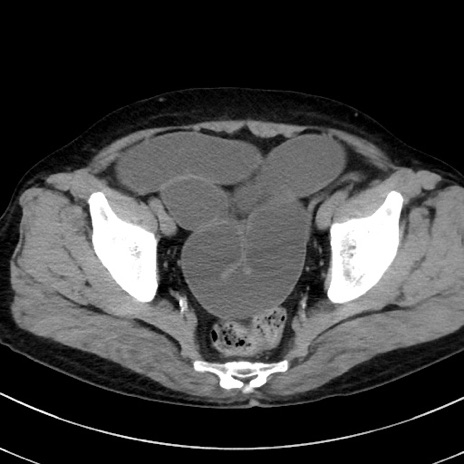

症例38(横断像)

【症例】70歳代 男性

【主訴】腹痛・嘔吐

【現病歴】昨晩より、嘔吐・腹痛あり。今朝になっても嘔吐あり。来院。

【既往歴】心臓バイパス手術、開腹胆摘、腸閉塞

【身体所見】BP 107/71mmHg、HR 116/min、腹部:平坦、軟、下腹部に軽度圧痛あり。反跳痛なし。

【データ】WBC 15100、CRP 0.32